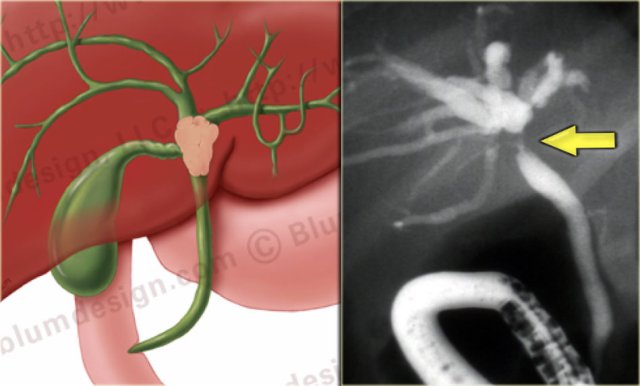

On the left an illustration and ERCP of a type IV-tumor with extention into the right and left duct.

A type IV tumor is unresectable.